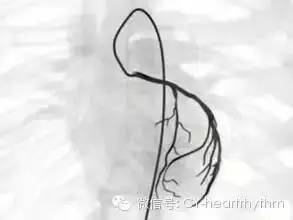

冠状动脉造影多取四肢动脉为入路,尤其经皮穿刺桡动脉最常用,也可穿刺股动脉或肱动脉(见下图)。

选择性冠状动脉造影是利用血管造影剂,通过特制的心导管经皮穿刺上肢桡动脉或者下肢股动脉,沿降主动脉逆行至升主动脉根部,然后探寻左或右冠状动脉口插入,注入造影剂,使冠状动脉显影,清楚地将整个左或右冠状动脉的主干及其分支的血管腔显示出来。

它可以了解血管有无狭窄病灶存在,对病变部位、范围、严重程度、血管壁的情况等作出明确诊断,决定治疗方案(介入、手术或内科治疗),还可用来判断疗效(见下图)。